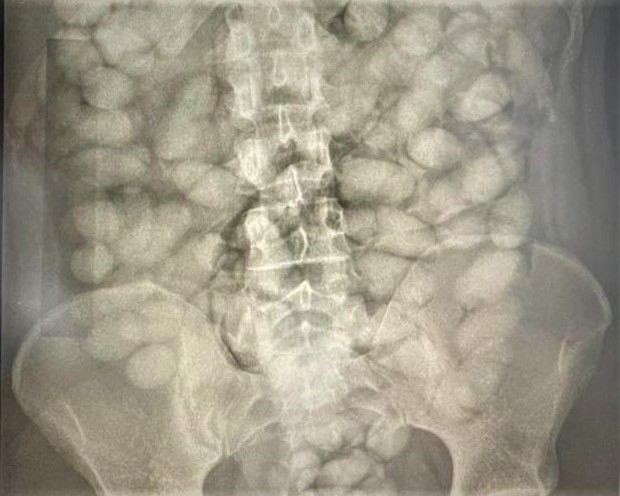

A Polícia Federal (PF) prendeu em flagrante, no Aeroporto Internacional de Viracopos, em Campinas (SP), dois homens que tentavam embarcar para Orly (França) com cápsulas ingeridas contendo cocaína.

Um dos presos é de origem húngara, de 37 anos, e ingeriu 110 dessas. O outro, um brasileiro de 23 anos, estava com 127 cápsulas da droga.

Ambos foram encaminhados ao Hospital Mario Gatti, para que recebam cuidados médicos até que sejam expelidas as capsulas – quando será possível definir a quantidade de droga encontrada.